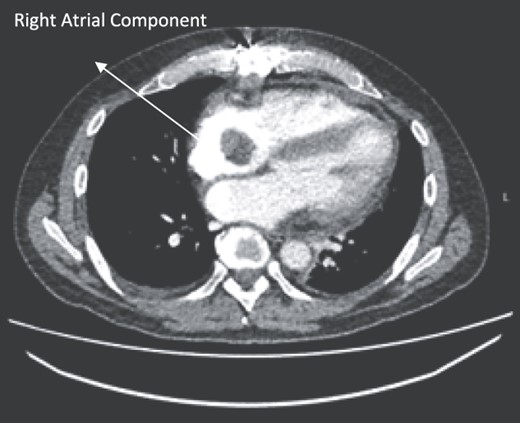

Follow-up CT scans were undertaken during chemotherapy that showed continued reduction in the size of the RA tumour, as demonstrated in Figs 4 and 5. The pericardial mass following chemotherapy is visualized in Fig. 6.

Post-operative CT scan during chemotherapy showing reduction of size RA bulk.